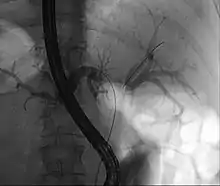

| Klatskin tumor during ERCP. Wires were inserted into the left and right biliary systems. Both parts were injected through a tube with contrast, but there is no contrast visible in the area of confluence of the two systems | |